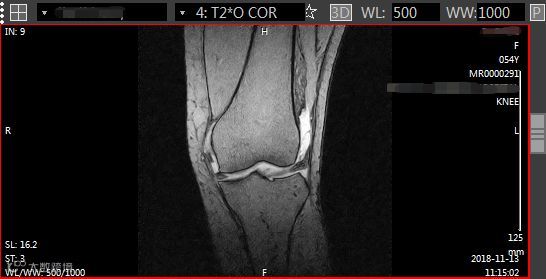

记得有一次,万里云平台上的某医院传来了患者膝关节的MR影像扫描资料,质控委员会看到图像后建议医院在扫描膝关节时要考虑扫冠状位T2WI脂肪抑脂和矢状位T2WI脂肪抑脂像,这样可以增加图像对比度,很好地显示外伤所造成的骨髓及软组织水肿,避免漏诊。质控委员会不放过任何一个可能影响患者影像诊断的细微点,以帮助医院正确规范扫描,准确诊断,满足临床治疗的需要。